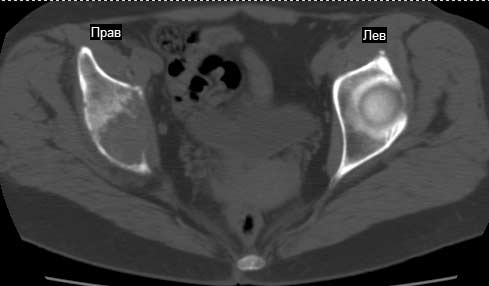

Сохранная по соматической патологии женщина ,47 лет. В 1996 г. установлен диагноз- cr левой молочной железы Т2N1Mo (2б)- проведено комплексное лечение- мастэктомия по Холстеду, ДГТ, 5 курсов ПХТ по схеме CMF. Сейчас менопауза уже 6-7 лет. В декабре 2004 года на профилактической остеосцинтиграфии с Тс99- выявлен единичный очаг повышенной фиксации препарата в зоне правой седалищной кости, рекомендована Рентгенография костей таза, выполнена- без патологии. УЗИ брюшной полости и Р-графия легких от конца апреля 2005 года - без патологии. Приблизительно 3 месяца назад появился болевой синдром в правом т/бедренном суставе с тенденцией к усилению. На рентгенограмме таза от мая 2005 года по заключению Рентгенолога очагов остеодеструкции не выявлено. Сегодня сделал ей Кт костей таза (картинки в приложении)- очаг деструкции в правой седалищной кости в зоне крыши вертлужной впадины.Что можно и нужно сделать? Жду советов, мнений, предложений по дальнейшей тактике ведения больной. С уважением, Корнев А.В.

Как я смог понять из данных анамнеза у Вашей матушки позднее прогрессирование рака молочной железы через 9 лет после лечения - солитарный метастаз в кости таза с высокой угрозой

Его мнение: в данный момент облучение не более 2000-3000 рад, через три недели операция по удалению процесса "кюретажным методом" затем ввести несколько спиц с резбой на конце в различных направлениях (создавая как бы внутренную арматуру) метод Harrington?, потом полость залить цементом, вариант костной пластики тоже не исключает.